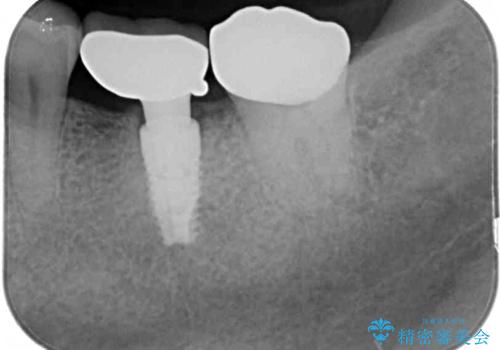

- 銀歯の装着されている奥歯がしみるとのことで来院された患者様です。

銀歯周辺の歯が欠けており、むし歯も進行している状態であったので、オールセラミッククラウンにて補綴治療を行うこととしました。